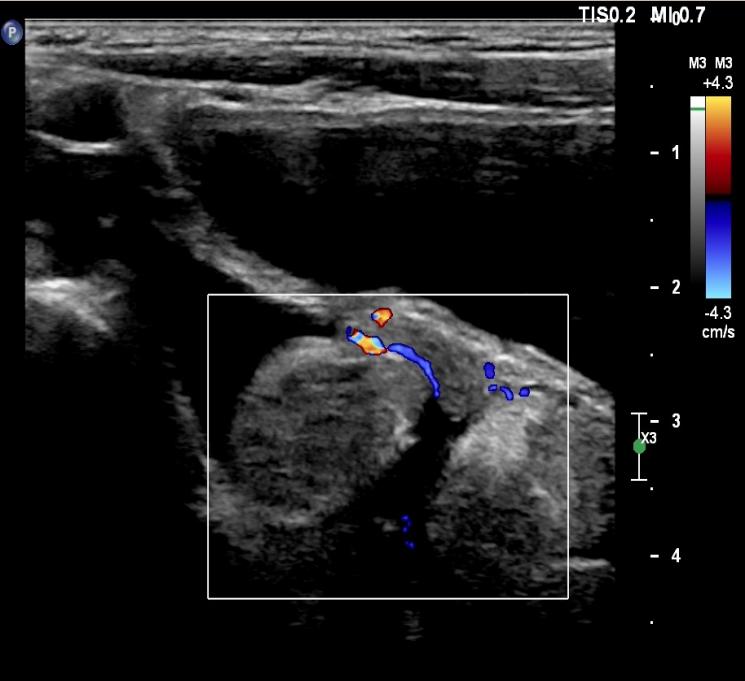

据西安市儿童医院公众号26日消息:5岁的彤彤(化名)因跳绳后下腹部疼痛难耐,当地医院初步诊断为急性阑尾炎。急诊来该院进一步复查B超,超声科医生却发现了更为严重的问题——卵巢扭转。

医院随即安排进行急诊手术,术中发现右侧卵巢发紫,顺时针扭转720°,即对右侧卵巢进行了切除。